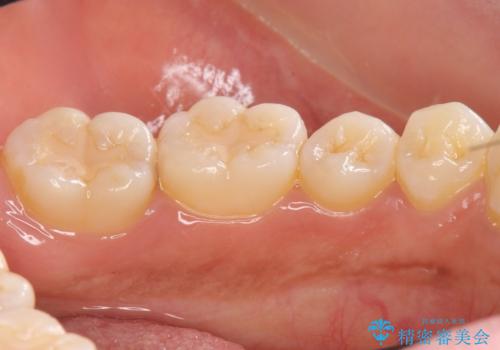

古い詰め物を取り、虫歯を除去して、合わせた形でセラミックインレーで治療しました。

- 14万円(内訳 左下67:セラミックインレー 7万円 x 2本)費用は治療当時の料金となります